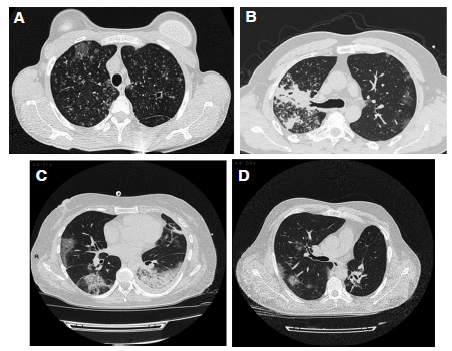

Respecto del diagnóstico de TB, en 15 casos (65%) se sospechó TB a partir de las imágenes obtenidas para evaluar el compromiso pulmonar por el COVID (Figura 1). Seis pacientes informaron antecedentes de tratamiento previo, incompleto en 4 de ellos (todos con TB activa) y 2 con lesiones secuelares (consideradas TB inactiva), uno con un aspergiloma intracavitario. La localización de la TB fue pulmonar en 18, pleural en 2 y meningitis, 1.

En la TC de tórax, en 18 pacientes (78%) se observaron concomitantemente a imágenes cavitarias (11 pacientes), nodulillares y micronodulillares, árbol en brote y derrame pleural (compatibles con TB); opacidades a predominio periférico en vidrio esmerilado, en algunos casos con tendencia a la consolidación y en ocasiones broncograma aéreo (compatibles con COVID-19 y eventual sobreinfección bacteriana) (Figura 1). La mayor extensión lesional de este último tipo de imágenes correspondió a una TB pleural que requirió internación breve en UTI sin necesidad de asistencia ventilatoria mecánica. La TB fue confirmada por baciloscopía en 17 casos; fue efectuado GeneXpert confirmatorio en 11; 2 fueron resistentes a rifampicina, considerados a los fines terapéuticos como multirresistentes (niños de 5 y 16 años, contactos de adultos con TB-MDR).